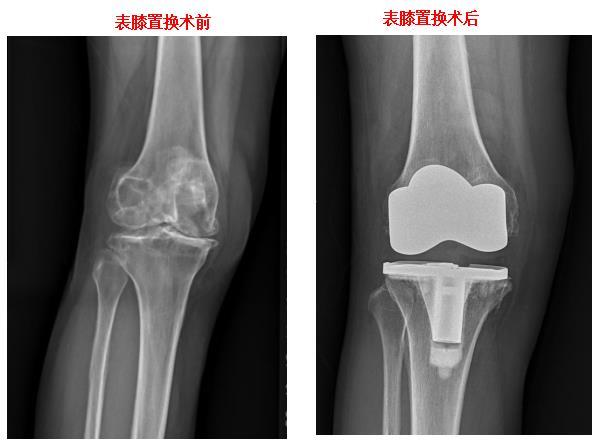

膝关节表面置换